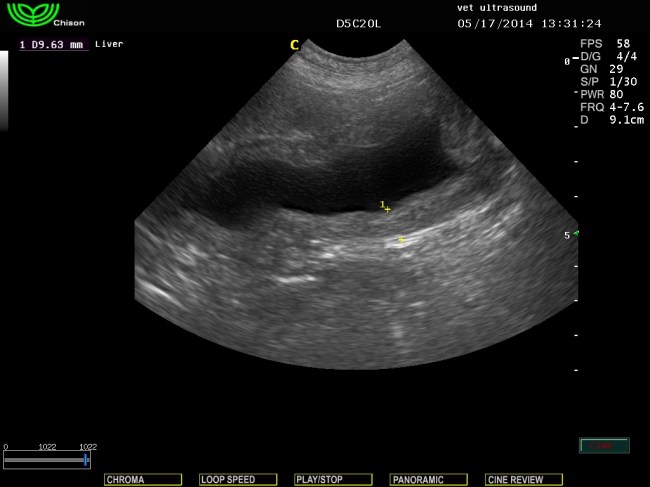

βλέπουμε το ακανόνιστο σχήμα της ουροδόχου μετά τον καθετηριασμό σε εγκάρσια τομή.